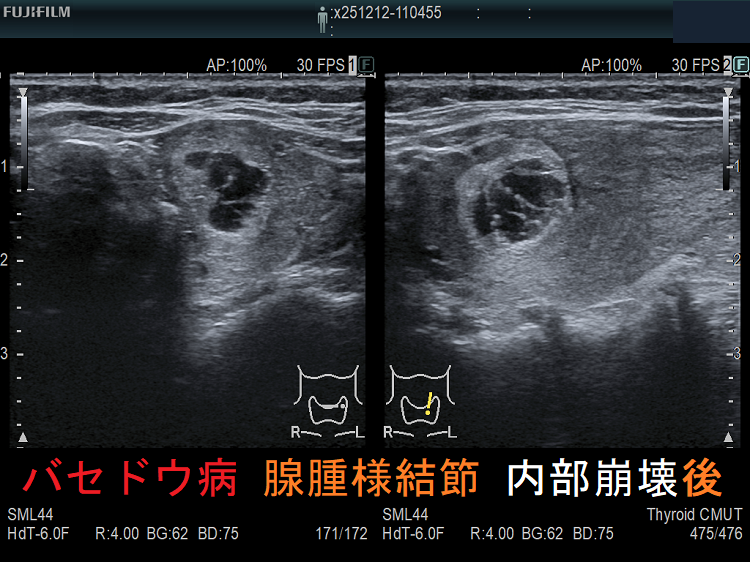

穿刺細胞診後内部融解

ケース①

ケース②